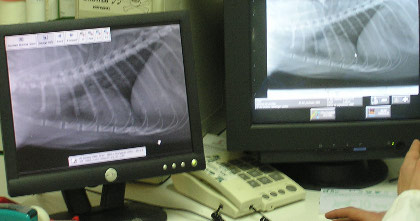

Toda la última tecnología al servicio de su mascota: